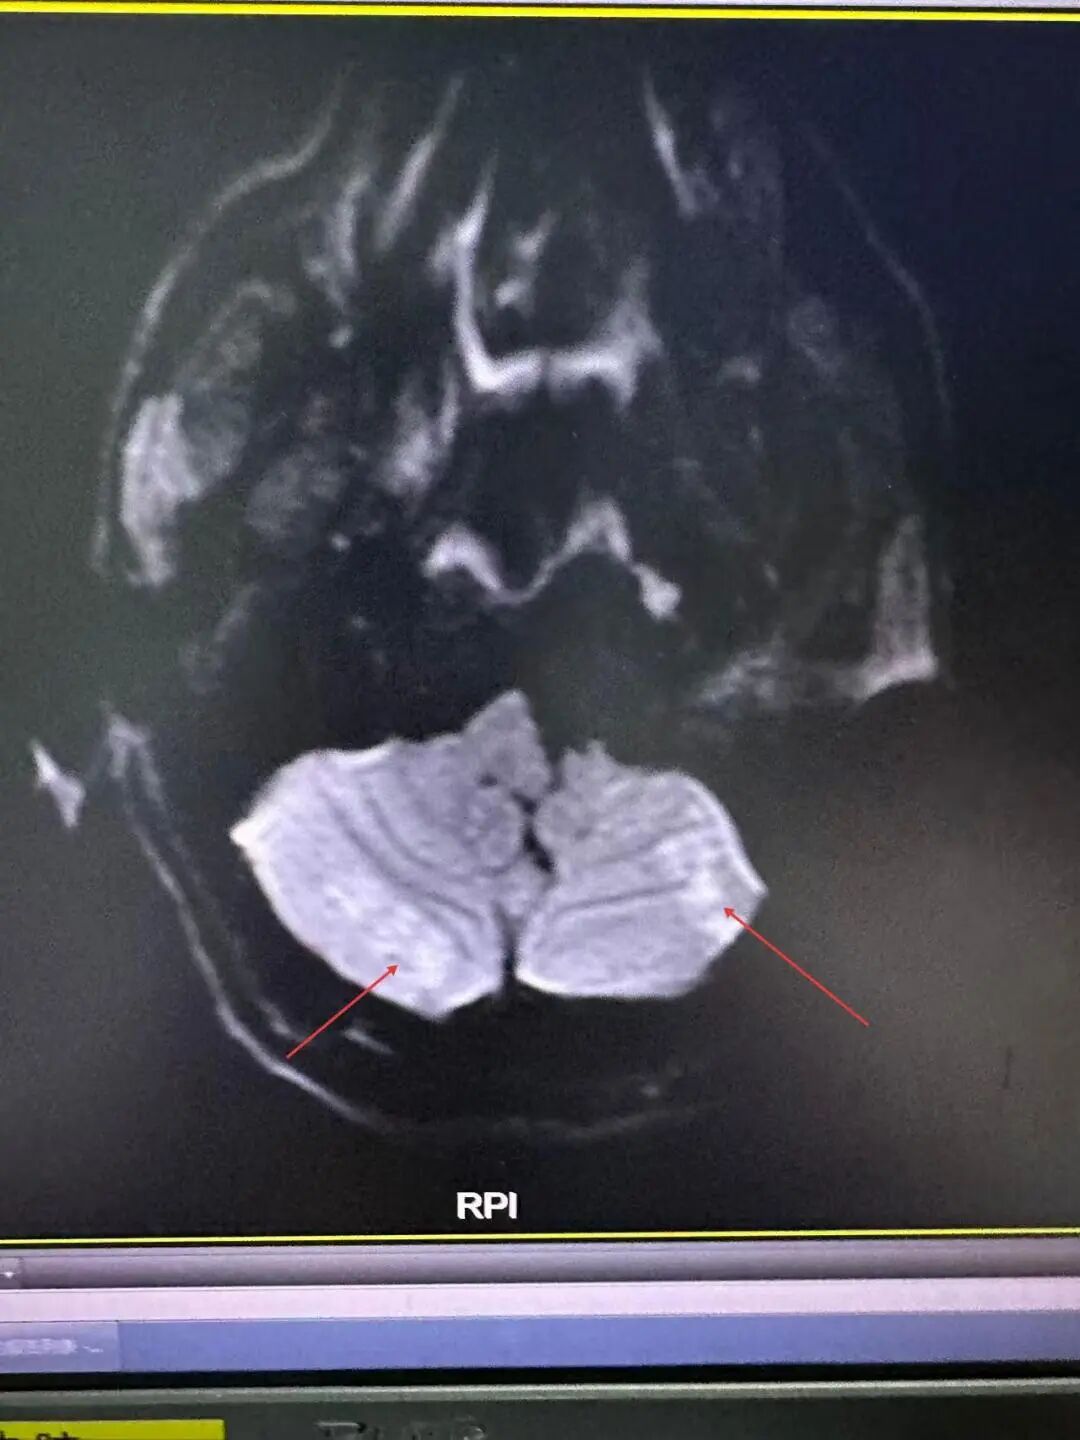

医护人员评估后立即启动卒中流程,颈动脉CTA提示是基底动脉重度狭窄,头颅卒中磁共振提示两侧大小脑散在新发脑梗。

(张先生发病时的颈动脉CTA及磁共振)